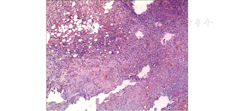

入院第2天,患者突然解黑便,量约500 mL,立即给予PPI抑酸、静脉注射尖吻蝮蛇血凝酶(商品名为苏灵)止血等治疗,行急诊胃镜检查,发现胃角和十二指肠球部溃疡(图3)。急查血常规示血红蛋白为118 g/L,故考虑消化性溃疡引起黑便可能性大,遂继续给予PPI、尖吻蝮蛇血凝酶等治疗,密切关注病情变化。入院第3天,患者出现鲜红色血便,量约2 000 mL,伴头晕、心慌,无腹痛,血压为86/60 mmHg,由于大量鲜血便,考虑为下消化道出血,立即在积极抗休克、PPI抑酸、输血、心电监护下行急诊肠镜检查,由于肠腔大量积血,影响视野,未发现出血点。遂又进行腹腔血管造影检查,发现右侧肝动脉分支造影剂蓄积,考虑假性动脉瘤,除此之外未发现造影剂流入肠道,见图4。经过全院会诊,考虑患者存在胆囊结石、胆囊炎等基础疾病,现出血原因不明,经积极保守治疗仍未控制出血,有外科手术指征,遂于11月21日行剖腹探查术,术中探查胃、小肠未见明显异常,胆囊壁增厚,并与结肠紧密相连,胆囊周围大量瘢痕组织增生,切开胆囊,可见大量血凝块,清除血凝块可见胆囊床侧胆囊内壁血管搏动性出血,缝扎胆囊内壁出血动脉,继续探查见胆囊与结肠肝曲形成内瘘,血液经瘘口流入肠腔,仔细分离胆囊结肠瘘(cholecystocolonic fistula, CCF)壁,常规切除胆囊,用可吸收线间断缝合关闭结肠瘘口,在距盲肠约25 cm末端回肠处行回肠双腔造口,腹膜、腹外斜肌腱膜、皮肤分别与肠管和肠系膜固定,0.9%氯化钠溶液清洗腹腔,放置引流管,清点器械、纱布无误后,关闭腹腔。术后病理诊断为CCF或慢性胆囊炎伴急性发作(图5)。患者术后恢复良好,随访至截稿日期,患者再无消化道出血表现。